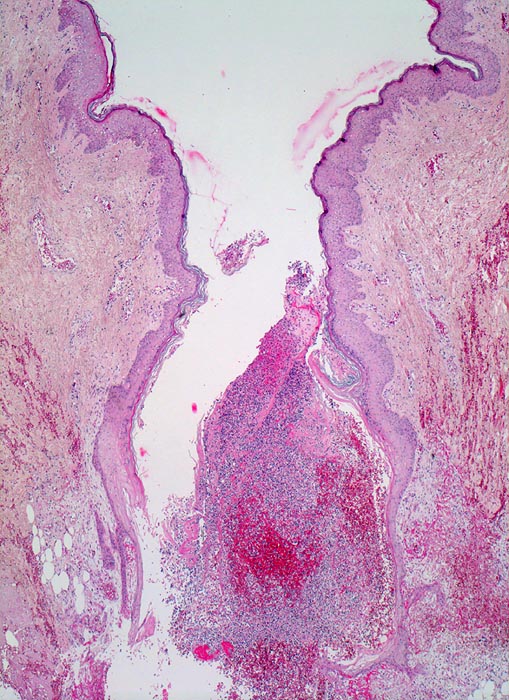

PathoPic – image database / PathoPic ID 3571 - Wundheilung

Wundheilung

Entzündung / Reparatur

Haut, Rumpf

Haut

Spaltförmiger Defekt des Plattenepithels, der sich fortsetzt in die darunterliegende Cutis. Der Spalt ist angefüllt mit Blut, Fibrin, Detritus (vorläufiger Propf). In den obersten Schichten massenhaft neutrophile Lenkozyten.

6 Tage alte Wunde am Abdomen nach Laparotomie.

Noch keine wesentliche Pflasterepithel-Regeneration möglicherweise als Ausdruck einer Wundheilungsstörung.

Histologie

25